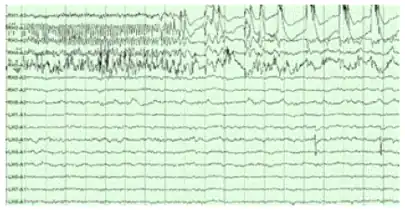

The hippocampus shows two major modes of activity, each associated with a distinct pattern of neural population activity and waves of electrical activity as measured by an electroencephalogram (EEG). These modes are named after the EEG patterns associated with them: theta and large irregular activity (LIA). The main characteristics described below are for the rat, which is the animal most extensively studied.[107]

The theta mode appears during states of active, alert behavior (especially locomotion), and also during REM sleep (dreaming).[108] In the theta mode, the EEG is dominated by large regular waves with a frequency range of 6 to 9 Hz, and the main groups of hippocampal neurons (pyramidal cells and granule cells) show sparse population activity, which means that in any short time interval, the great majority of cells are silent, while the small remaining fraction fire at relatively high rates, up to 50 spikes in one second for the most active of them.[109][110] An active cell typically stays active for half a second to a few seconds. As the rat behaves, the active cells fall silent and new cells become active, but the overall percentage of active cells remains more or less constant. In many situations, cell activity is determined largely by the spatial location of the animal,[111] but other behavioral variables also clearly influence it.

The LIA mode appears during slow-wave sleep (non-dreaming), and also during states of waking immobility such as resting or eating.[108] In the LIA mode, the EEG is dominated by sharp waves that are randomly timed large deflections of the EEG signal lasting for 25–50 milliseconds. Sharp waves are frequently generated in sets, with sets containing up to 5 or more individual sharp waves and lasting up to 500 ms. The spiking activity of neurons within the hippocampus is highly correlated with sharp wave activity. Most neurons decrease their firing rate between sharp waves; however, during a sharp wave, there is a dramatic increase in firing rate in up to 10% of the hippocampal population.[112]

Theta rhythm

The underlying currents producing the theta wave are generated mainly by densely packed neural layers of the entorhinal cortex, CA3, and the dendrites of pyramidal cells. The theta wave is one of the largest signals seen on EEG, and is known as the hippocampal theta rhythm.[114] In some situations the EEG is dominated by regular waves at 3 to 10 Hz, often continuing for many seconds. These reflect subthreshold membrane potentials and strongly modulate the spiking of hippocampal neurons and synchronise across the hippocampus in a travelling wave pattern.[115] The trisynaptic circuit is a relay of neurotransmission in the hippocampus that interacts with many brain regions. From rodent studies it has been proposed that the trisynaptic circuit generates the hippocampal theta rhythm.[116]

Sharp waves

During sleep or during resting, when an animal is not engaged with its surroundings, the hippocampal EEG shows a pattern of irregular slow waves, somewhat larger in amplitude than theta waves. This pattern is occasionally interrupted by large surges called sharp waves.[122] These events are associated with bursts of spike activity lasting 50 to 100 milliseconds in pyramidal cells of CA3 and CA1. They are also associated with short-lived high-frequency EEG oscillations called "ripples", with frequencies in the range 150 to 200 Hz in rats, and together they are known as sharp waves and ripples. Sharp waves are most frequent during sleep when they occur at an average rate of around 1 per second (in rats) but in a very irregular temporal pattern. Sharp waves are less frequent during inactive waking states and are usually smaller. Sharp waves have also been observed in humans and monkeys. In macaques, sharp waves are robust but do not occur as frequently as in rats.[113]